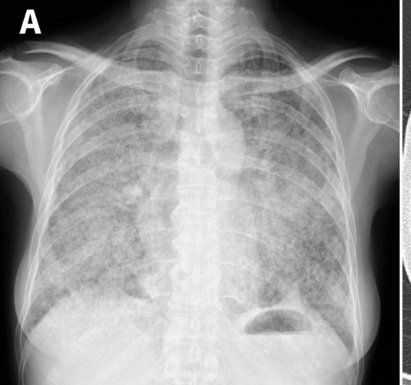

A 55-year-old, nonsmoking woman

Diagnosis? Image

Chest radiography and computed tomography showed a miliary pattern of many small nodules throughout all lung fields Image